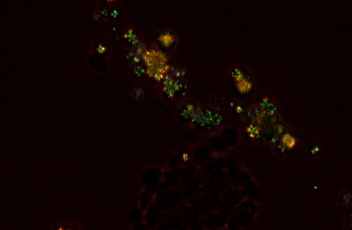

落射荧光

紧凑型落射荧光附件采用了专用的噪声终结机制,允许弱荧光标本与巨大的清晰度和亮度抓获。该过滤器的炮塔可以容纳四个过滤立方体,并改变它们很简单。高光学性能的物镜的落射荧光成像,包括CFI Plan Apochromat Lambda系列和CFI Plan Fluor系列,是可用的。

落射荧光附件和激发块